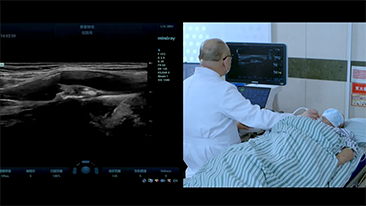

Mindray Resona Genel G?rĂŒntĂŒleme ??zĂŒmleri, kapsaml? alt b?lĂŒm uygulama problar? ve verimli klinik uygulama ara?lar? arac?l???yla, klinisyenlerin daha do?ru ve verimli tan? ve tedavi sonu?lar? elde etmesine yard?mc? olur.

GĂŒnĂŒmĂŒzde t?bbi ortam daha karma??k hale geldi, zorlu vakalar?n say?s? ve i? yĂŒkleri artt?.